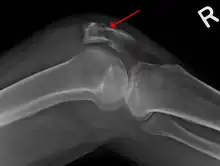

A fracture of the patella seen on a lateral view

Diagnosis is based on symptoms and confirmed with X-rays.[3] In children an MRI may be required.[3]